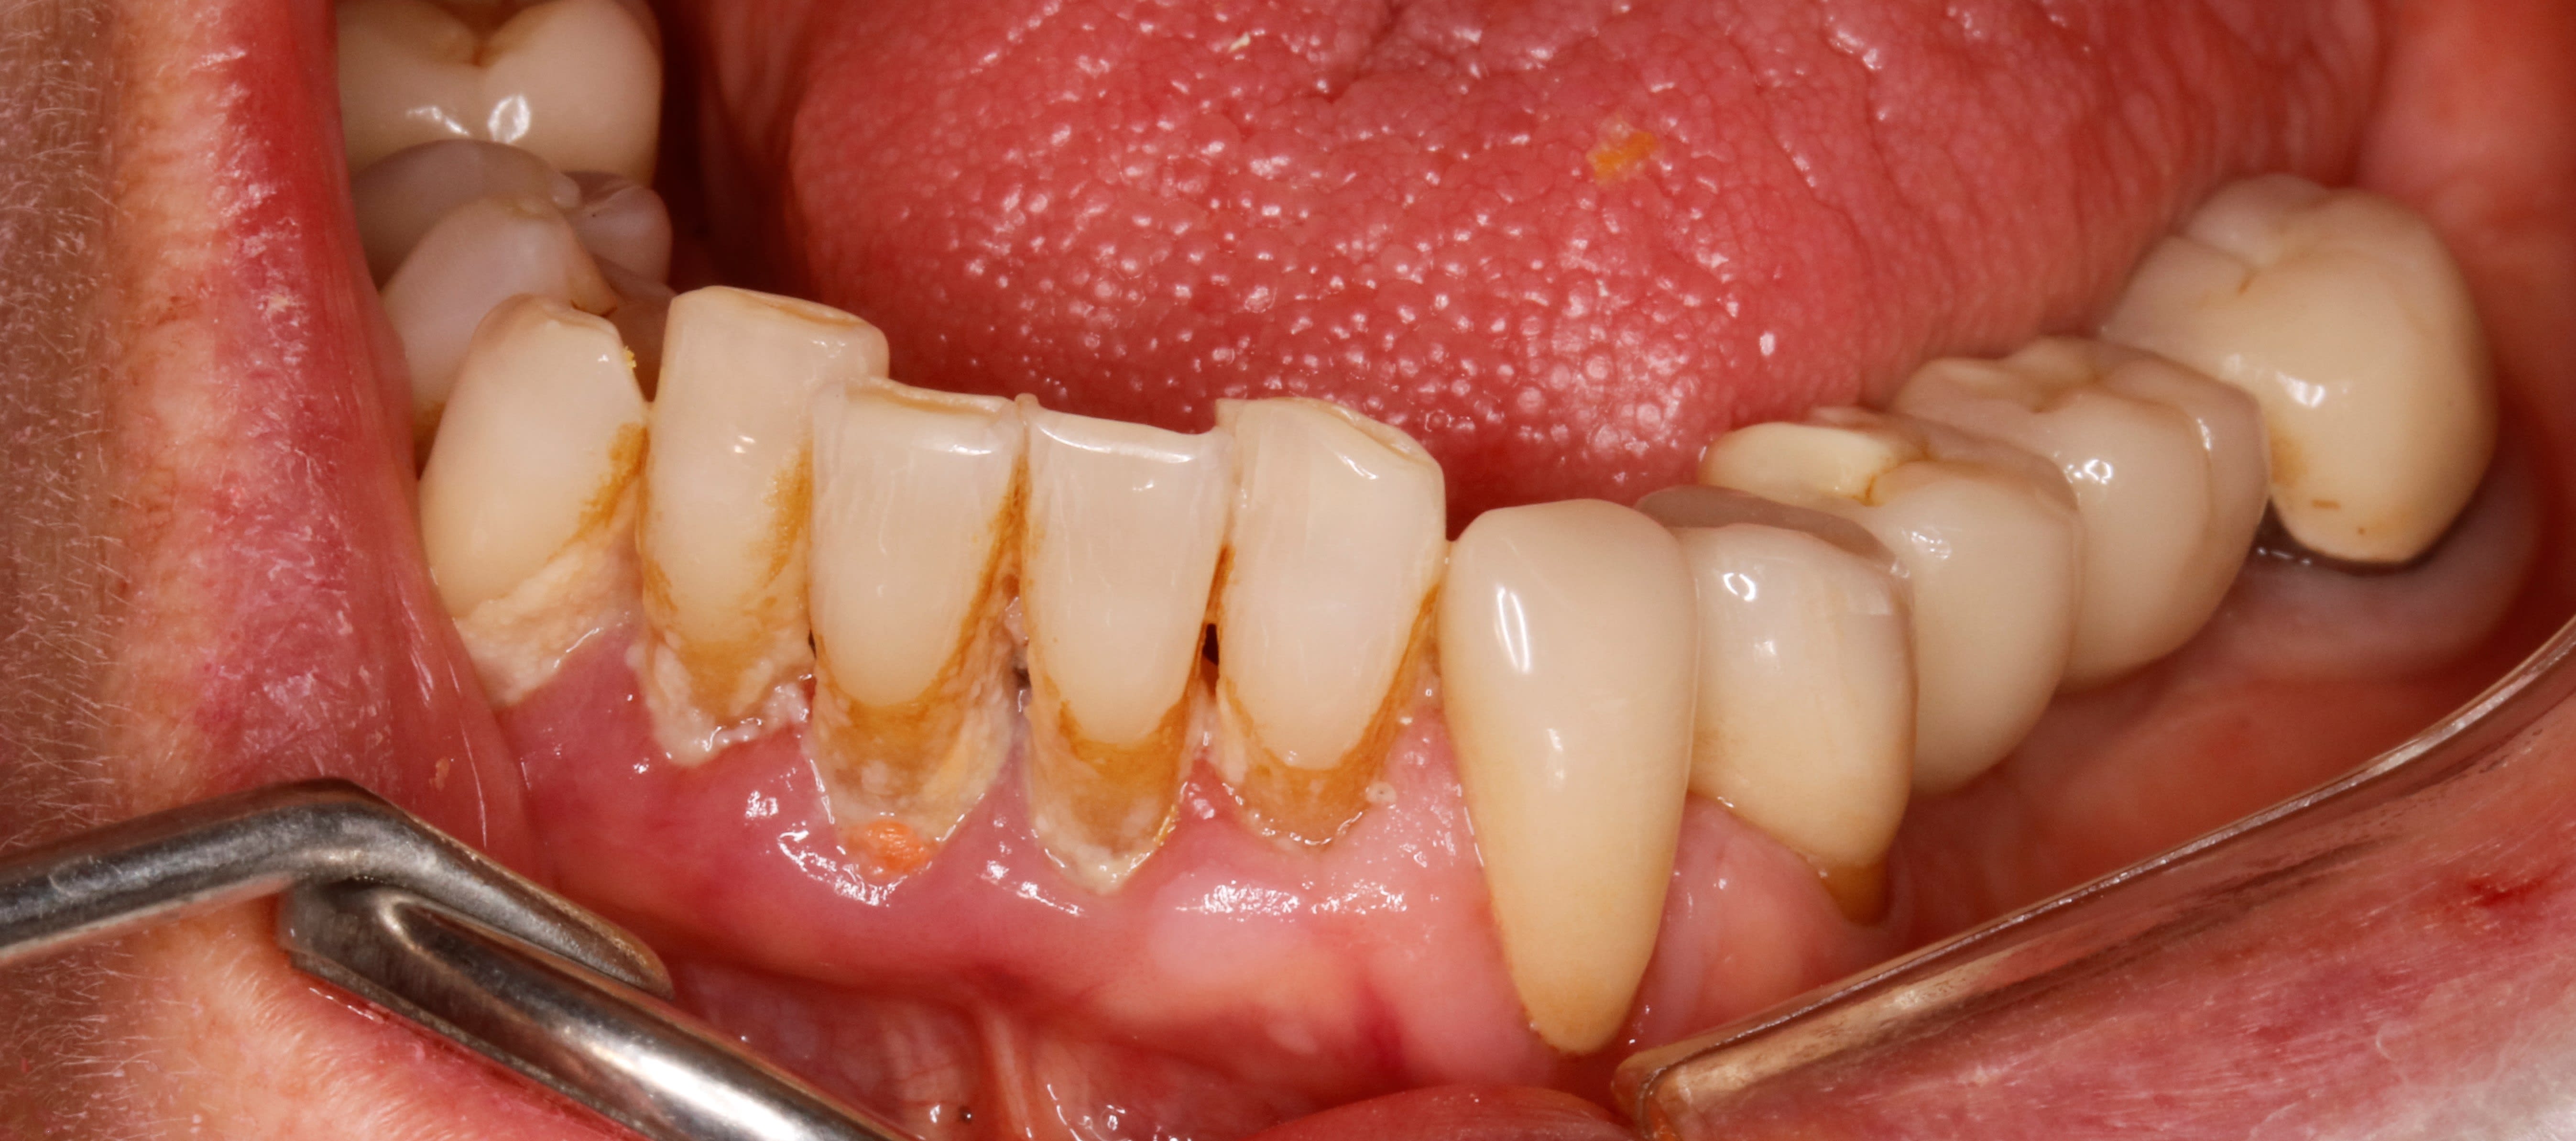

et là c est mardi passé , donc 8 ans apres et elle a donc 85 ans . j en profite pour lui refaire sa 26 .

et là il me vient 2 remarques qui sont flagrantes .

" Y'a de la plaque partout, sauf sur tes cerams? "

eh oui ç est la 1ere chose , et c est flagrant .surtout quand il n y a pas de metal , ici ce sont des @max

meme sur la 34 ou il y a une récession , ç est nickel .

alors tu me diras par exemple tel coté elle a mal au bras , et elle ne se brosse pas bien , ..., mais regarde la 24 pareil propre alors que le secteur 20 n est pas top

j ai tjs dit que la paro sans la prothese ç est du pipo en exagerant .

le fait de faire un curetage périphérique a la fraise grain fin du cément ben ça fait tjs du bien .deja pcq tu fais tout le tour , tu enlèves du tartre et du cément infiltré en proximal , ce que tu ne peux pas faire sans prothèse .

je pense que si j avais fait faire de l ortho classique par un pro sans prothese finale on aurait pas eu ça .

d autant qu il y aurait eu , d une façon classique une contention .

t imagines une hygiène pareille avec un fil comme ce serait pourri ? :-)

et j en viens à la 2eme chose que je remarque :

ç est que sans contention , sans solidarisation , ça n a pas bronché . je n ai pas perdu un point de contact .

je n ai meme pas eu de fracture de compo au niveau des angles

donc je maintiens que si c est bien équilibré la contention ne sert à rien . meme si c est une occlusion pipée comme ici .